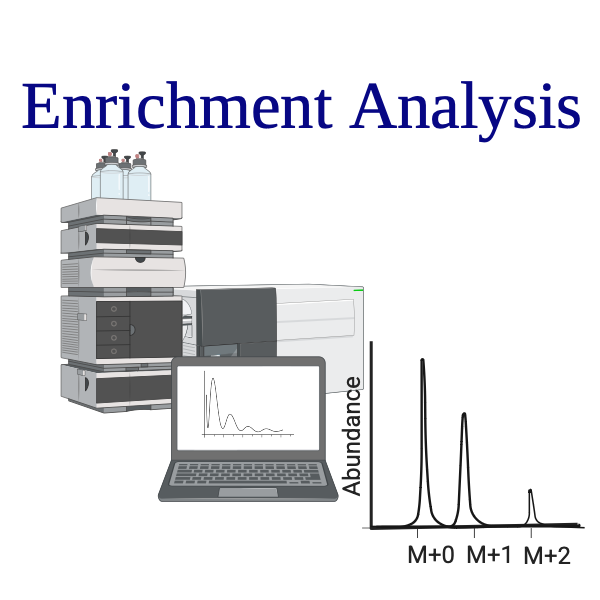

Step (3)

Analyze with LC-MS or NMR

Step (4)

Interpret metabolic flux using custom-built modeling software (e.g., SUMOFLUX)